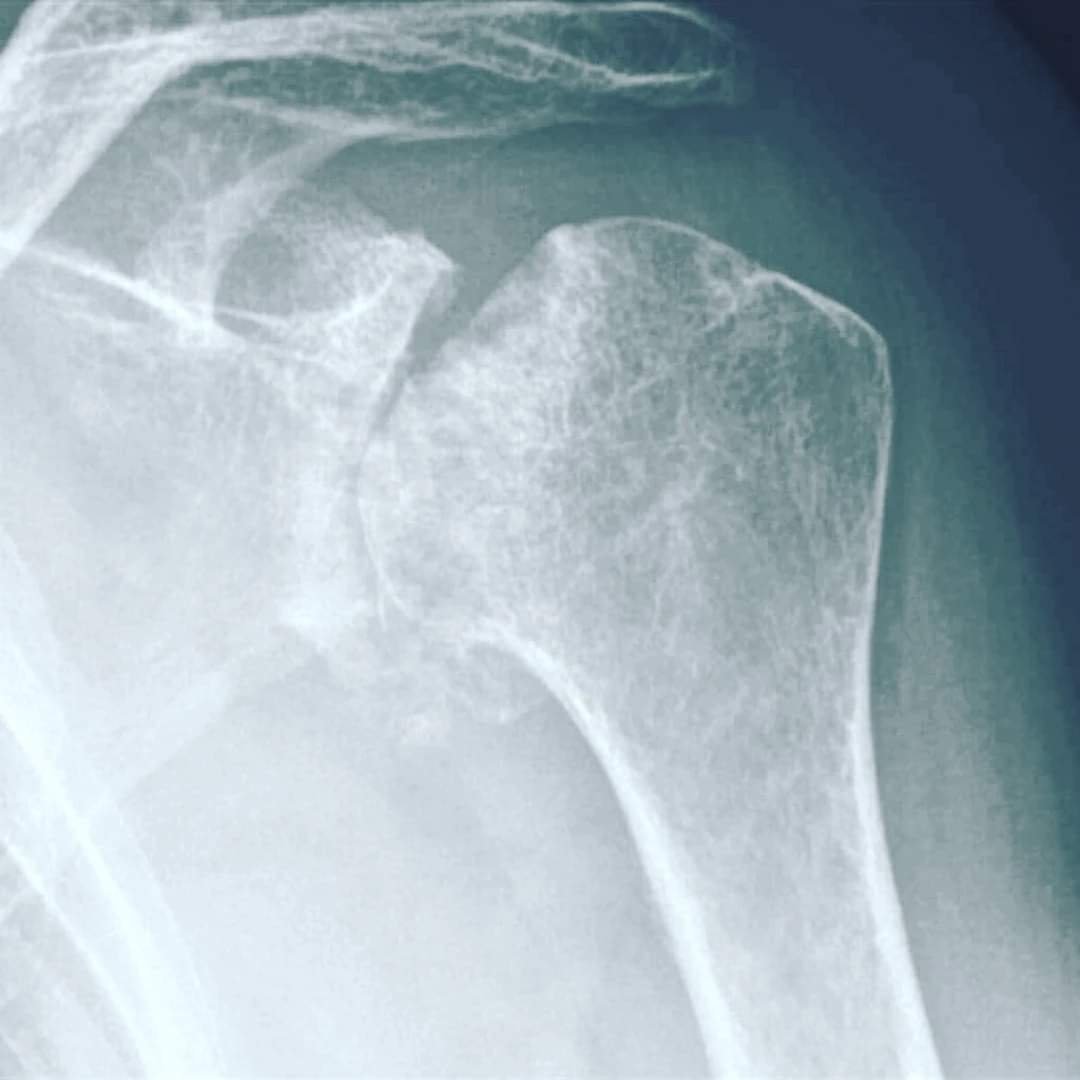

На цьому знімку плечового суглоба – деформація кісткової частини 4 ступіню. Зарадити нічим вже не можна. Не чекайте цього! Виправити, відновити, покращити функцію суглоба, хребта, враженого навантаженнями, чи віковими змінами, пов’язаними зі старінням – МОЖЛИВО! Гарна новина в тому, що Ви, при наявності будь-яких проблем с хребтом та суглобами, маєте змогу зараз, вчасно звернутись до лікаря-фахівця, який зупинить незворотні зміни. Запропонує метод відновлення, який, без перебільшення може врятувати Ваш хребет, чи суглоб, від заміни хірургом на штучний…